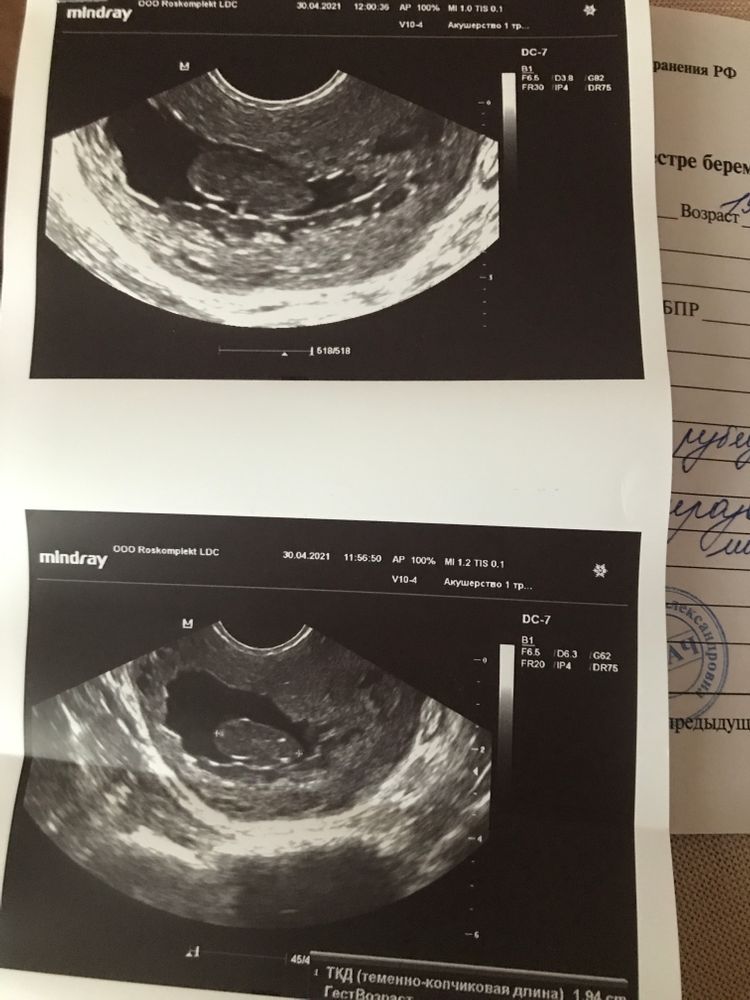

сегодня была на узи и знаете что?! В матке неразвивающаяся беременность.....ужас! Сроком 8 недель! Как так?! Как могли не заметить второе пя?! Это просто кошмар. То есть я хожу с этим уже столько времени..я в панике конкретной. Выпью азитромицин и 4 мая меня должны отправить на чистку...я не знаю как прожить эти 4 дня.

Sakubona, фиг знает🤷♀️ Есть фото и описание узи? Окончательный ответ даст гистология. Настаивайте, чтобы чистку делали под контролем гистероскопа и как следует осмотрели полость матки после выскабливания. А не вслепую опять тупо вакуумом отсосали.

Sakubona, заключение никакое вообще. Ни описания нормального, ни размеров, ничего. На мой оооочень непрофессиональнй взгляд - это полип. И хгч вам надо бы сдать.

По виду ПЯ уже деформированное. У организма на этот счет есть три варианта, самопроизвольный выкидыш, мумификация (такое тоже бывает) и может само рассосаться. Когда из двойни один замирает, а это не редкость, то второй плод остается обычно в таком вот как бы мумифицированном состоянии до родов, либо рассасывается.